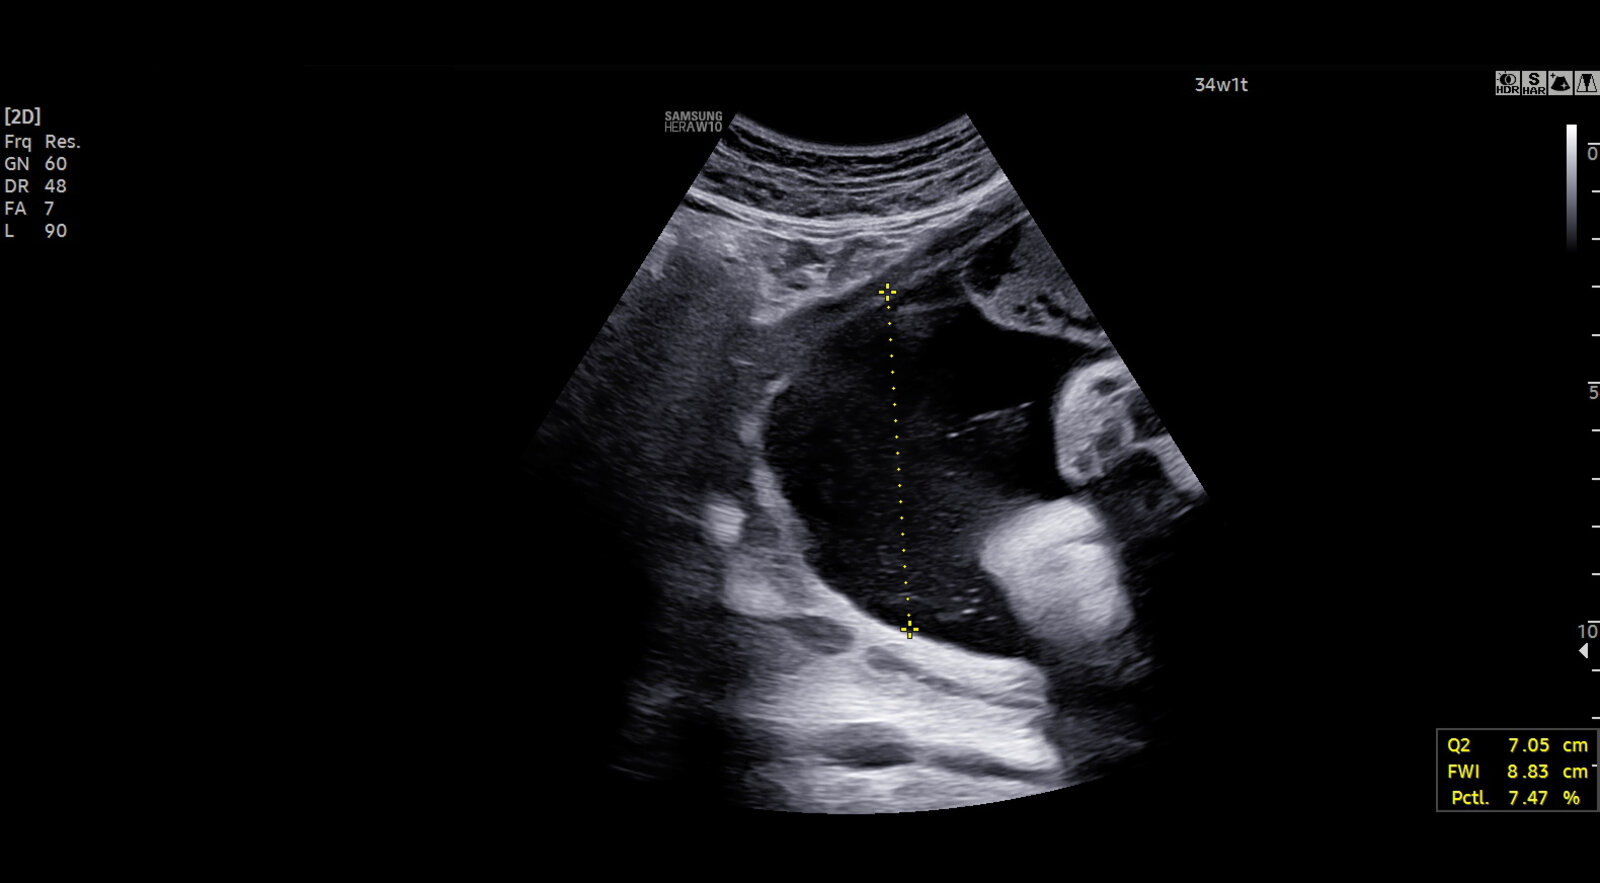

Amniotic fluid volume - 2 points if a single deepest vertical pocket > 2 cm with a horizontal dimension ≥ 1 cm

- Oligohydramnios: The presence of oligohydramnios, regardless of the BPP score, may necessitate delivery or close monitoring due to the increased risk of fetal compromise.

- Normal Results: A reactive NST (indicative of fetal well-being) combined with a DVP > 2 cm

- Abnormal Results: A nonreactive NST or a DVP ≤ 2 cm